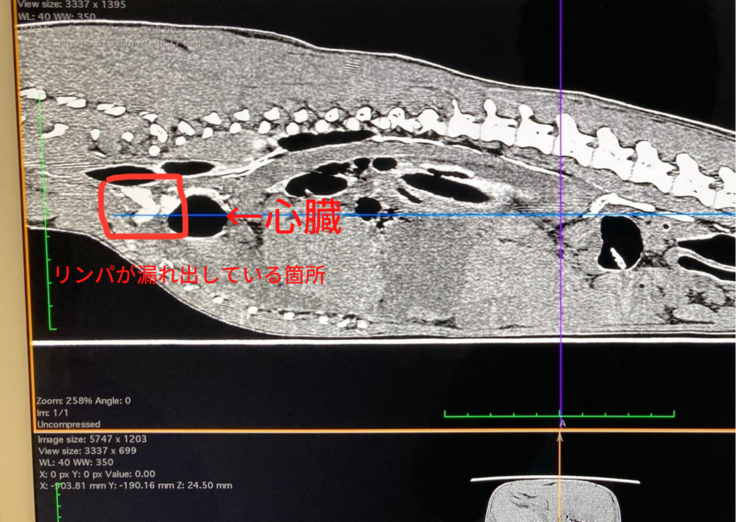

この日は、CTや造影剤を用いた大掛かりな検査をしていただきました。

心臓付近にリンパ液が溜まっているのが分かります。(赤い四角で囲った部分)

(※病院より診療明細書の掲載許諾は得ておりますが、個人を特定するお名前は伏せさせていただいております。)